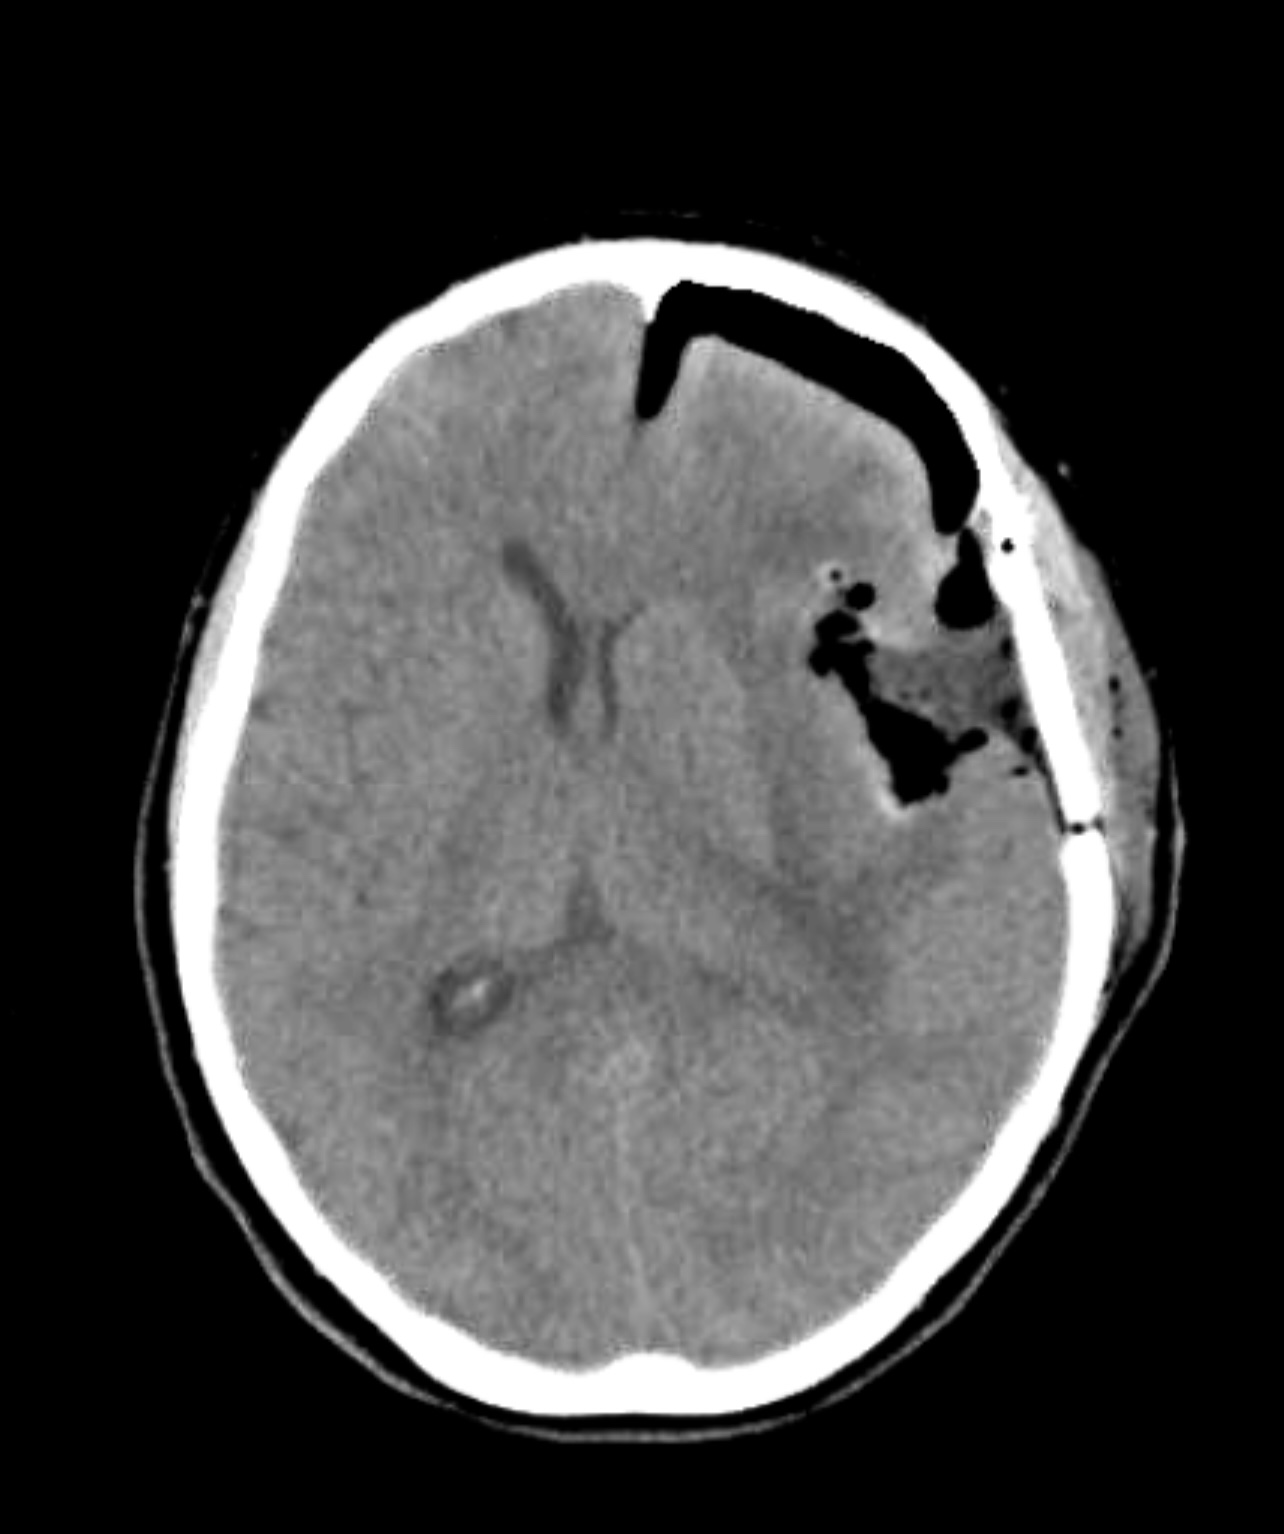

This leads us to today. We got a new MRI on September 2nd (2 days ago) and visited the doctor this morning. He showed us the images of the new MRI which did show a slight increase in the size of the affected area, but no new blood vessel growth in the new scan.

In the first image, you can see the spot on the left side of the image (right side of the brain since the images are reversed), but on the second image, you can see the area where the spot is does NOT show any highlights or additional blood flow.